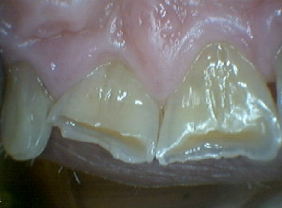

Worn Translucent Incisal Edges, Translucency Corrected with Hybrid Resins